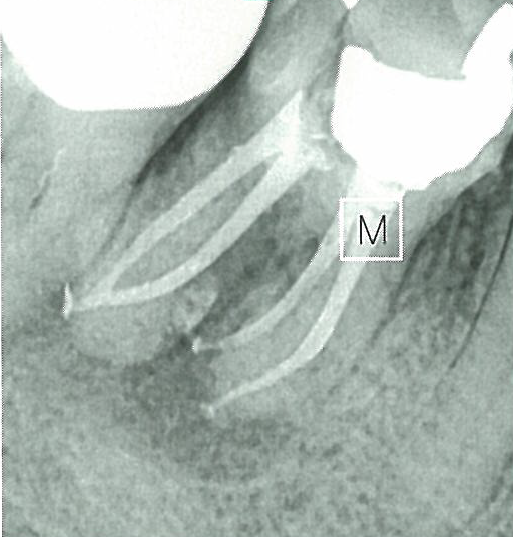

신경치료가 어려운 데에는 여러가지 이유가 있습니다. 먼저 근관 내부가 보이지 않기 때문입니다. 근관 입구의 위치는 육안으로 확인이 가능하나 실제 치료에 가장 중요한 근관의 길이나 만곡, 방향 등을 보면서 확인할 수가 없습니다. 방사선 사진을 통해 약간의 힌트를 얻을 수는 있습니다. 하지만 근본적으로 치과의사들은 치료 도중에 근관을 직접 눈으로 볼 수 없습니다. 그런데 이렇게 근관이 보이지도 않는 환경에서 근관을 따라 정해진 길로만 가야 합니다. 정해진 길에서 조금만 벗어나거나 새로운 길을 만들면 안 됩니다. 이 길을 파악하는 것은 쉽지 않습니다. 그것은 환자마다 치아의 모양이 다르고, 또 치아마다 근관의 모양이 다르기 때문입니다. 따라서 어떤 신경치료라도 함부로 쉽다고 말할 수 없습니다. 근관의 모양을 완벽하게 알 수 있는 상황은 없기 때문입니다.